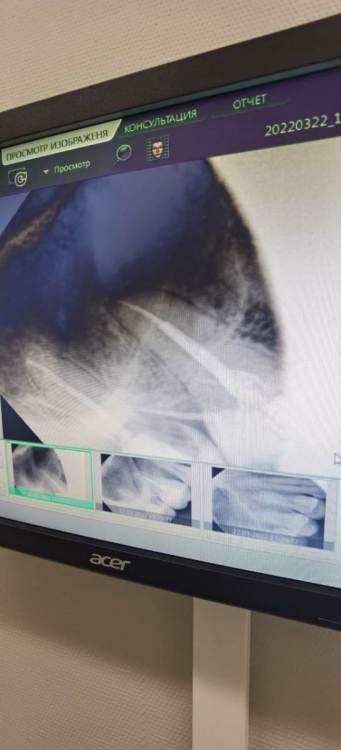

Irouil Опубликовано 26 марта, 2022 Поделиться Опубликовано 26 марта, 2022 Показать снимки, для начала 1 Ссылка на комментарий

Avrog Опубликовано 27 марта, 2022 Автор Поделиться Опубликовано 27 марта, 2022 13 часов назад, Irouil сказал: Показать снимки, для начала Ссылка на комментарий